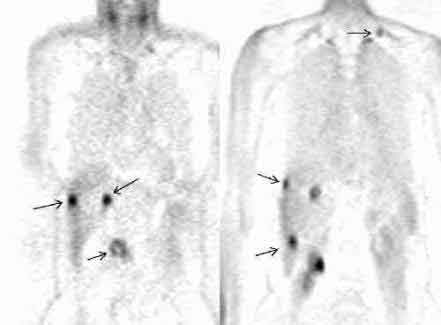

Рис. 3. Применение позитронной эмиссионной томографии при раке поджедлудочной

железы. Множественные очаги гиперфиксации 18F-ФДГ у пациента с аденокарциномой

головки поджелудочной железы и метастазами опухоли (фронтальные срезы).

Слева. Срез на уровне головки поджелудочной железы. Стрелками

отмечены опухоль головки (нижний очаг) и два метастаза в печени.

Справа. Срез на уровне почки. Стрелками отмечены три метастаза в печени

и метастаз в надключичный лимфатический узел.